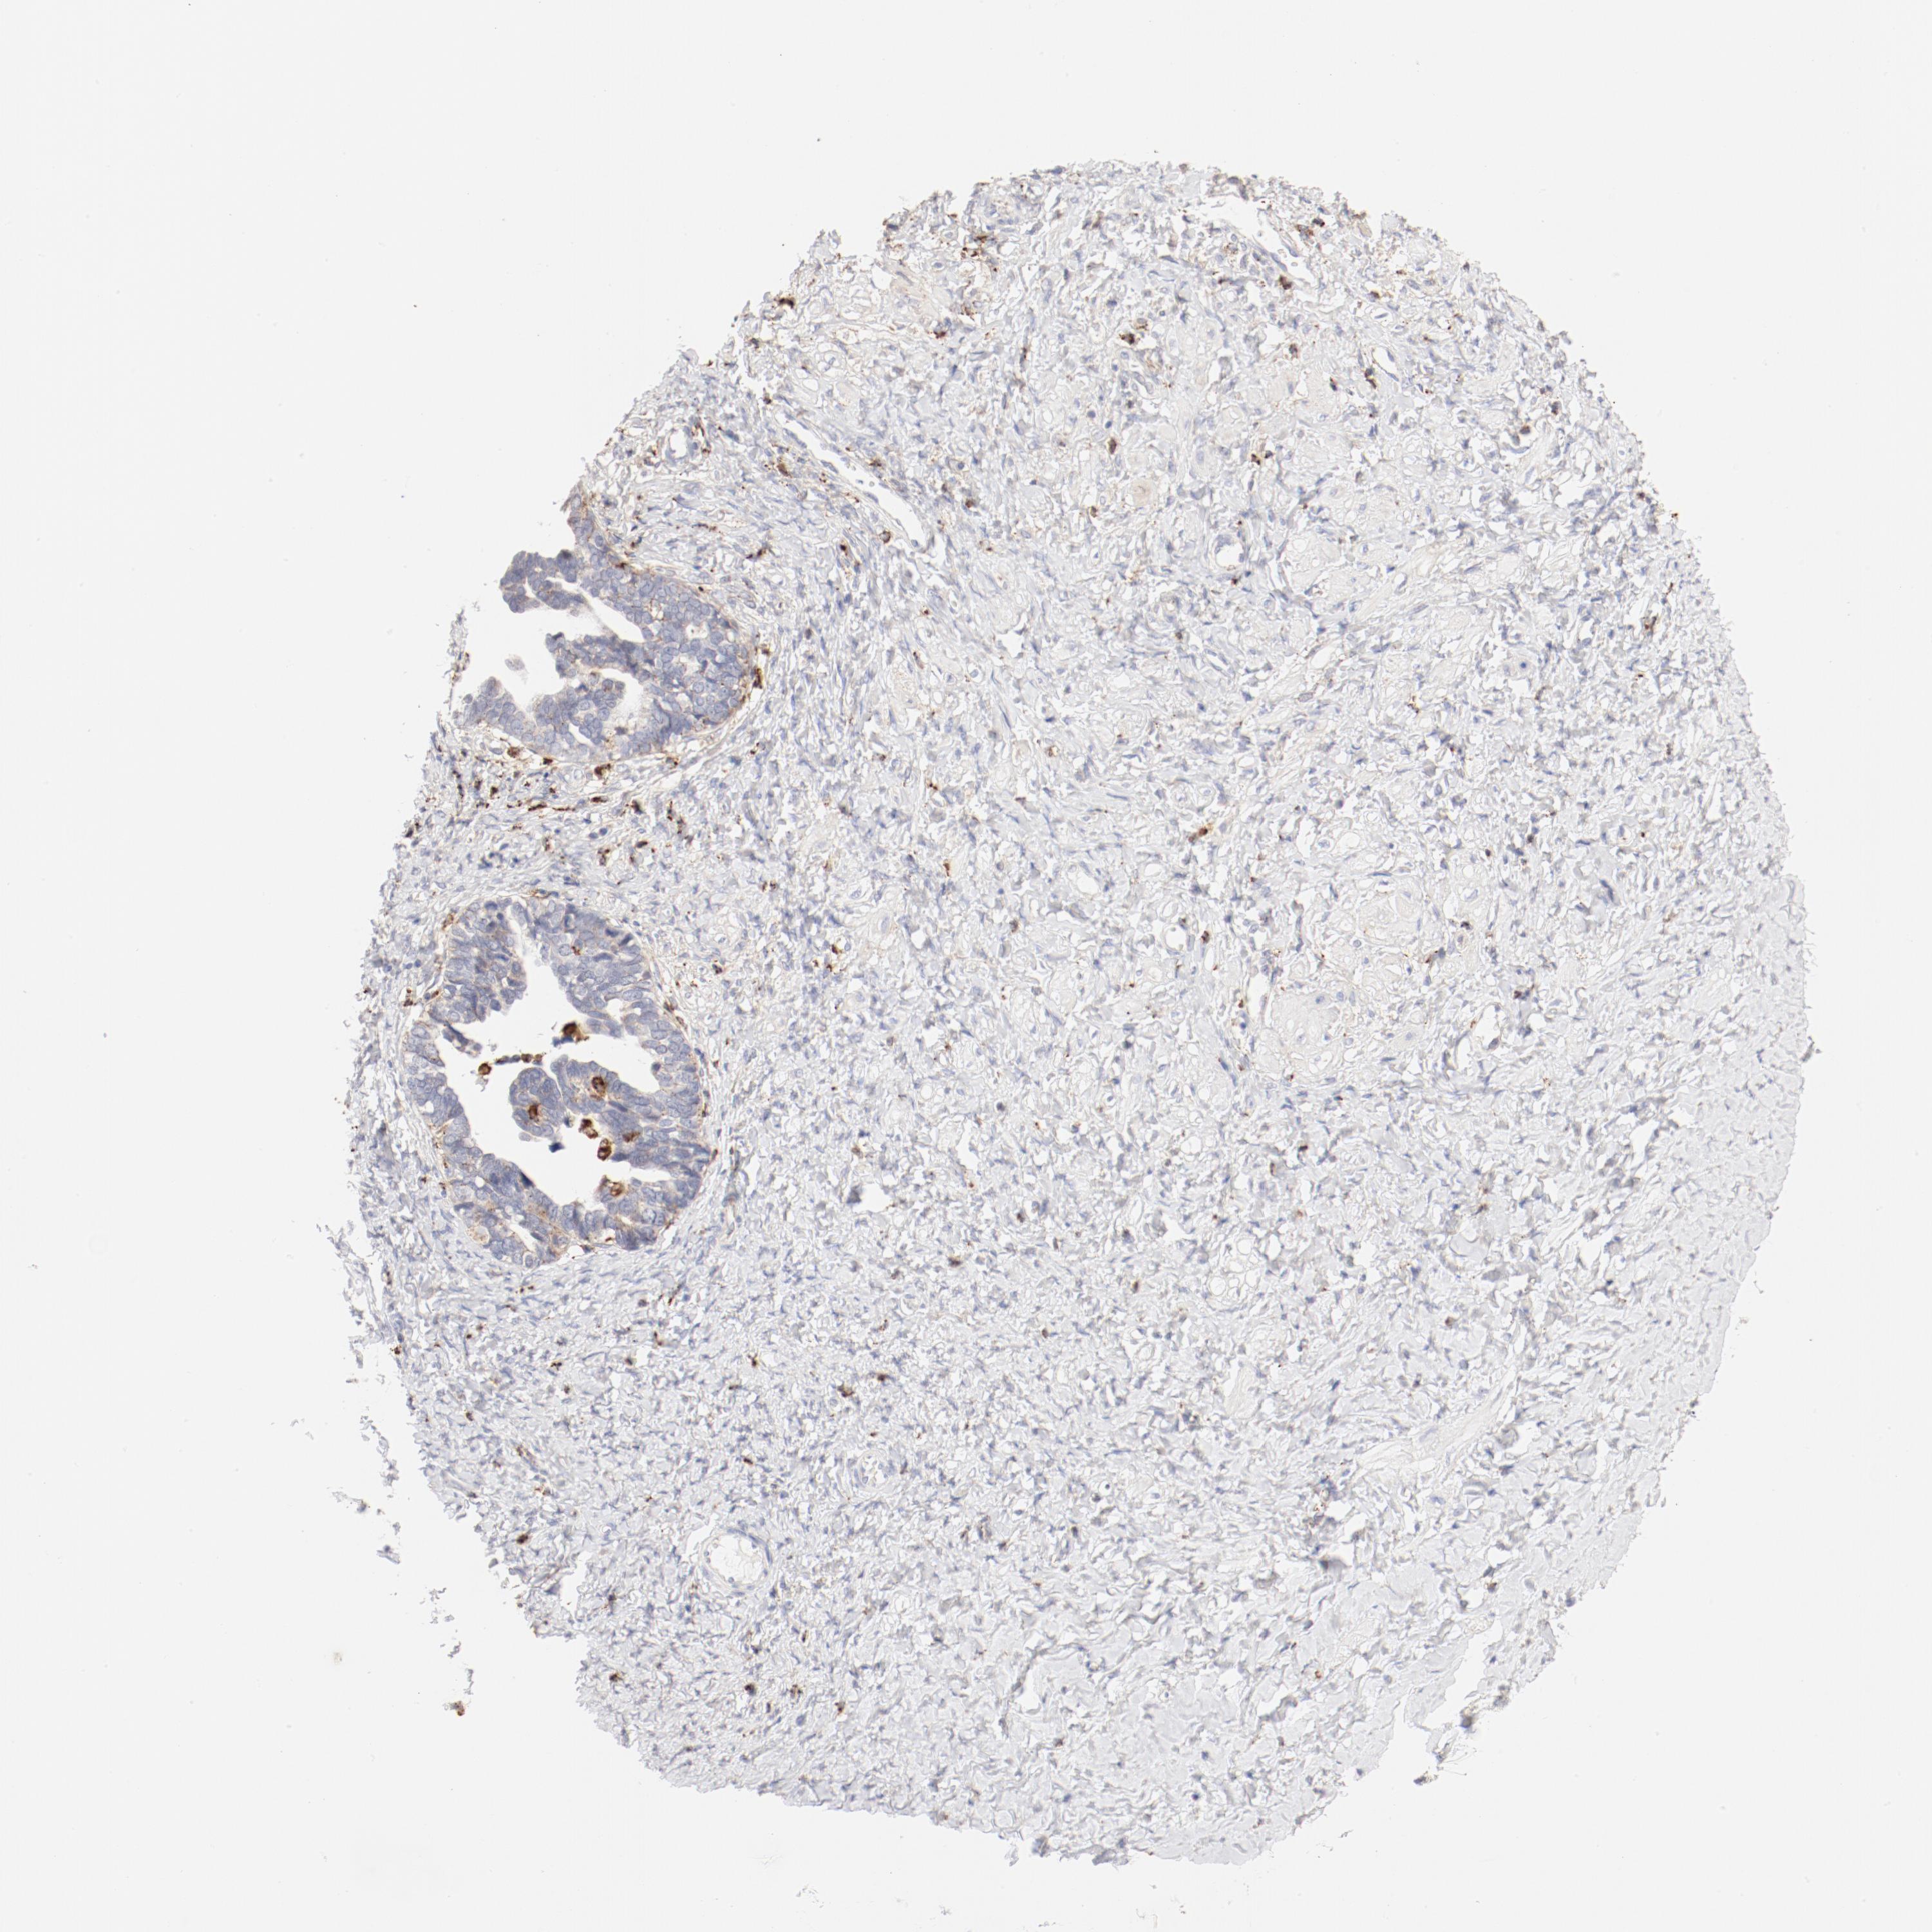

OVARIAN CANCER - Protein expressioni

A mouse-over function shows sample information and annotation data. Click on an image to view it in a full screen mode. Samples can be filtered based on level of antibody staining by selecting one or several of the following categories: high, medium, low and not detected. The assay and annotation is described here.

Note that samples used for immunohistochemistry by the Human Protein Atlas do not correspond to samples in the TCGA dataset.

Antibody stainingi

Antibody staining in the annotated cell types in the current human tissue is reported as not detected, low, medium, or high, based on conventional immunohistochemistry profiling in selected tissues. This score is based on the combination of the staining intensity and fraction of stained cells.

Each image is clickable and will lead to virtual microscopy that enables deeper exploration of all samples and also displays staining intensity scores, fraction scores and subcellular localization as well as patient and tissue information for each sample.

Antibody HPA003524

Antibody CAB000458

Staining

High

Medium

Low

Not detected

Intensity

Strong

Moderate

Weak

Negative

Quantity

>75%

75%-25%

<25%

None

Location

Nuclear

Cytoplasmic/membranous

Cytoplasmic/membranous,nuclear

Cystadenocarcinoma, mucinous, NOS

Carcinoma, endometroid

Cystadenocarcinoma, serous, NOS